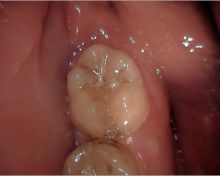

- Prova del dente trapiantando nell'alveolo ricevente

- Alloggiamento del dente trapiantando nell'alveolo ricevente e splintaggio con gli elementi contigui